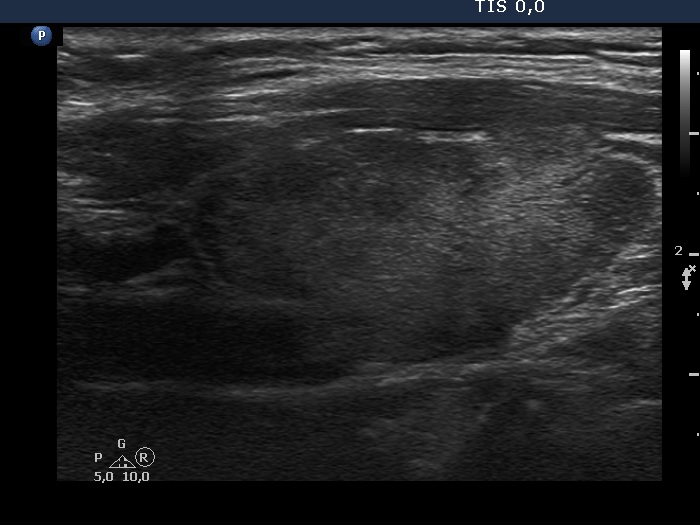

Patient referred for evaluation of thyroid nodule - final diagnosis Hashimoto's thyroiditis - Case 25.

Follow-up investigation two years after the first visit (ultrasonographic picture 7)

Left lobe, another longitudinal scan.